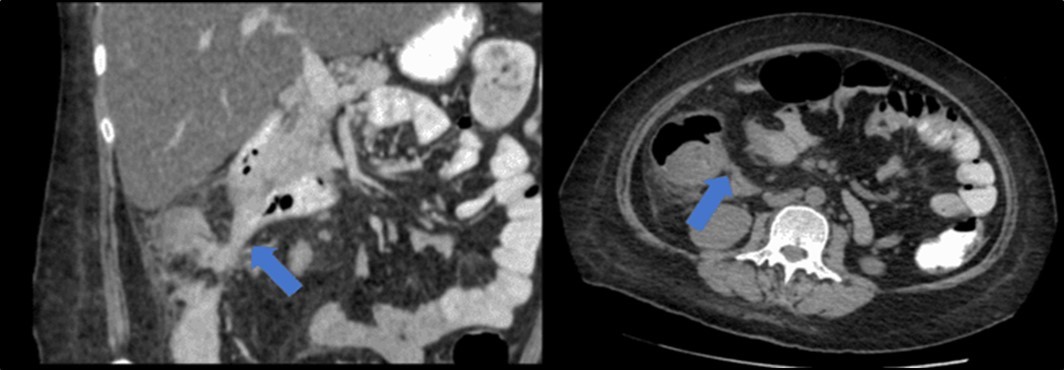

There was no evidence of malignancy or IBD seen during both endoscopic procedures. Computed tomography (CT) scan of the whole abdomen was done which showed inflammatory changes involving the cecum and adjacent duodenum and ileum with coloenteric fistulae. There was noted progression of abdominal lymphadenopathies as well as ascites. Main consideration was an infectious disease process (i.e. TB) (Figure 2, Figure 3, Figure 4 to Figure 5).

Figure 3.Coronal and axial view of the abdomen, the blue arrows pointing towards the suggestive communication to the ileum.

Coronal and axial view of the abdomen, the blue arrows pointing towards the suggestive                     communication to the ileum.